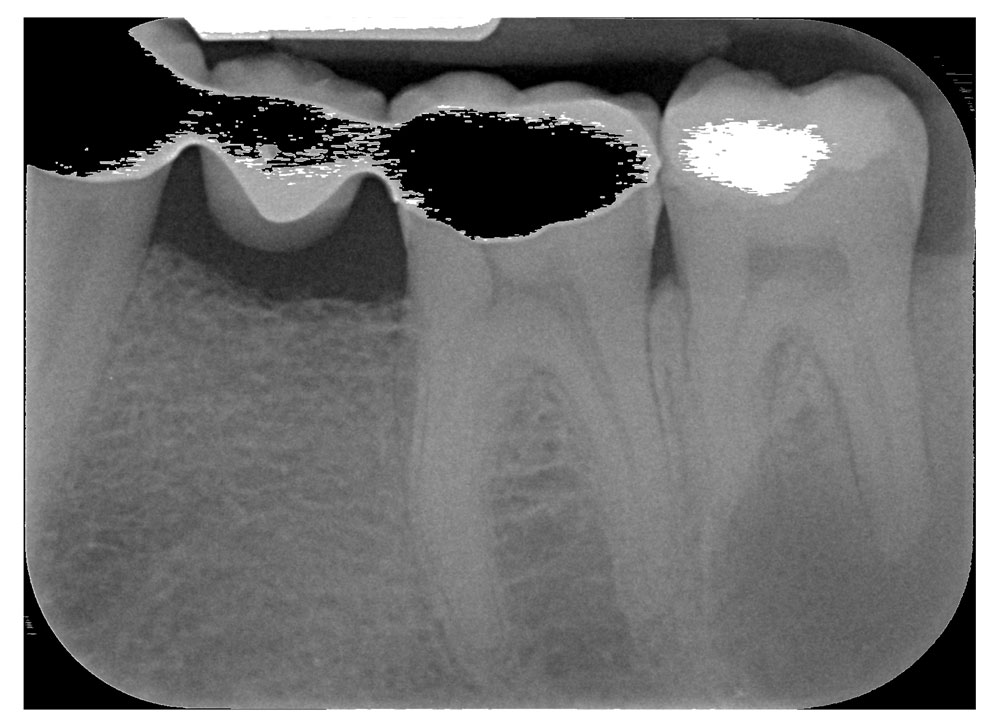

Endodonzia: è la branca che si occupa della detersione, sagomatura e otturazione dei canali delle radici dei denti.

Quando una carie penetra fino al nervo del dente è necessario intervenire devitalizzando, per prevenire ascessi dolorosi o infezioni asintomatiche (granulomi) che possono rilasciare tossine pericolose per gli organi vitali quali cuore fegato reni.

Talvolta è necessario reintervenire su devitalizzazioni precedenti in quanto non corrette e quindi fonte di possibili ulteriori infezioni.

L’esame radiografico, fondamentale per porre diagnosi in odontoiatria, in endodonzia diviene irrinunciabile perché è l’unico strumento che ci permette di “vedere” all’interno della radice del dente. È quindi molto importante la possibilità di effettuare lastre con apparecchiature digitali che emettono una dose di raggi ridotta rispetto a un radiografico tradizionale.